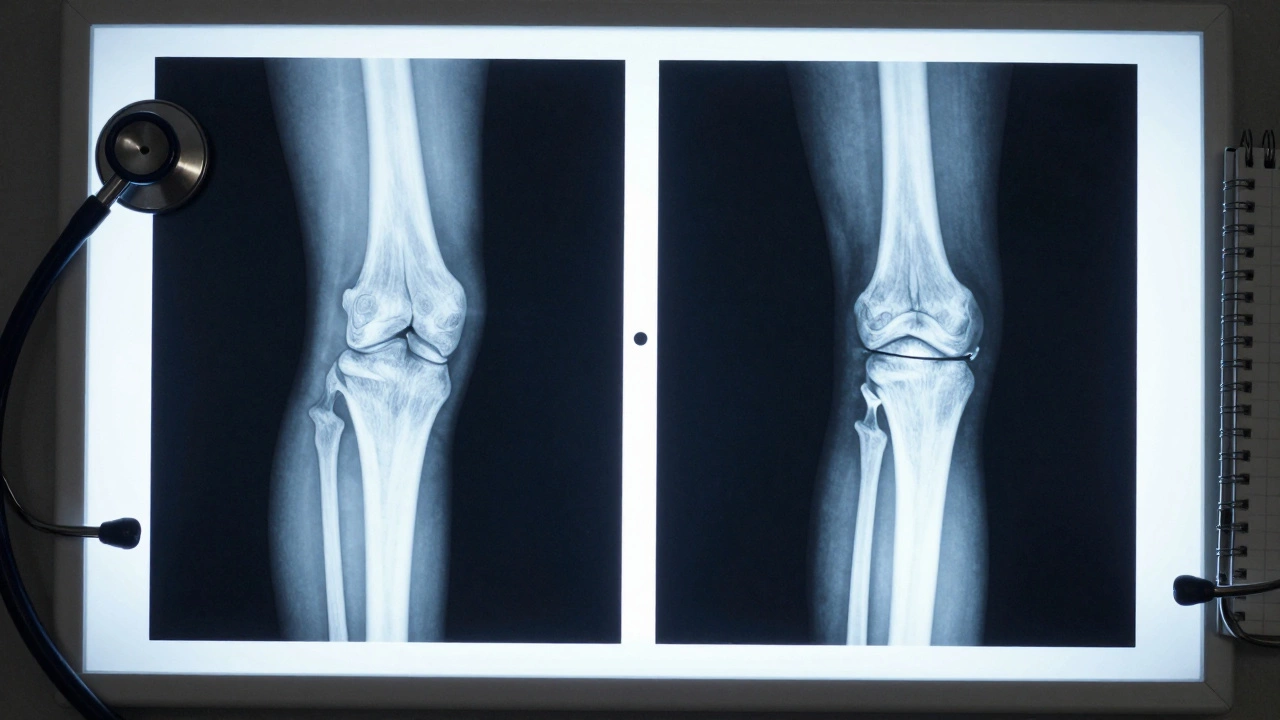

Some people think they need a knee replacement because they have “bone-on-bone” on an X-ray. But X-rays don’t show pain. They show structure. Two people can have the same X-ray and feel completely different. That’s why your symptoms matter more than the scan.

Side-by-side X-rays showing healthy knee versus bone-on-bone arthritis.

Viscosupplementation (hyaluronic acid shots) works for some, especially in early stages. But if your X-ray shows the space between your bones is nearly gone-less than 2 millimeters-you’re past the point where injections help. That’s not a guess. That’s measurable on an MRI or weight-bearing X-ray.